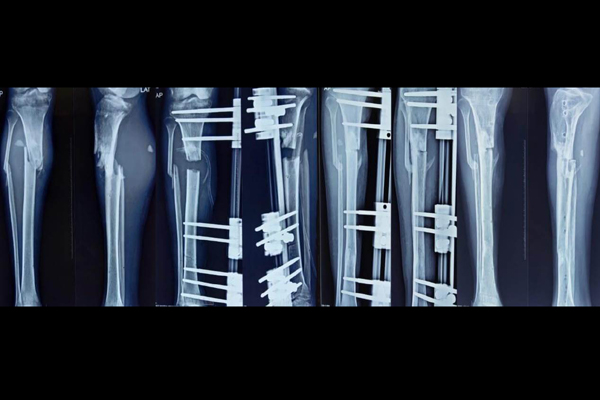

Reiterate the benefits of choosing the hospital for Orthopaedic, Physiotherapist, and Pathology care. Invite visitors to take the first step towards a pain-free life by clicking the call-to-action button.